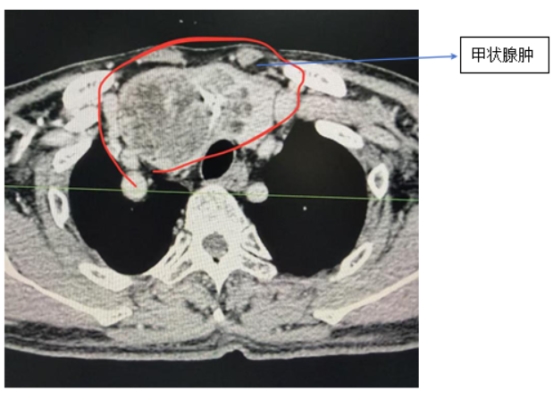

近日,62岁患者邹某某因严重呼吸困难,慕名来到衡阳市中心医院乳甲外科,找到科室主任罗琼博士求诊。经CT检查发现,邹某某患有胸骨后巨大甲状腺肿,气管被严重挤压偏移,最窄处仅剩正常管径的三分之一,手术风险极高。